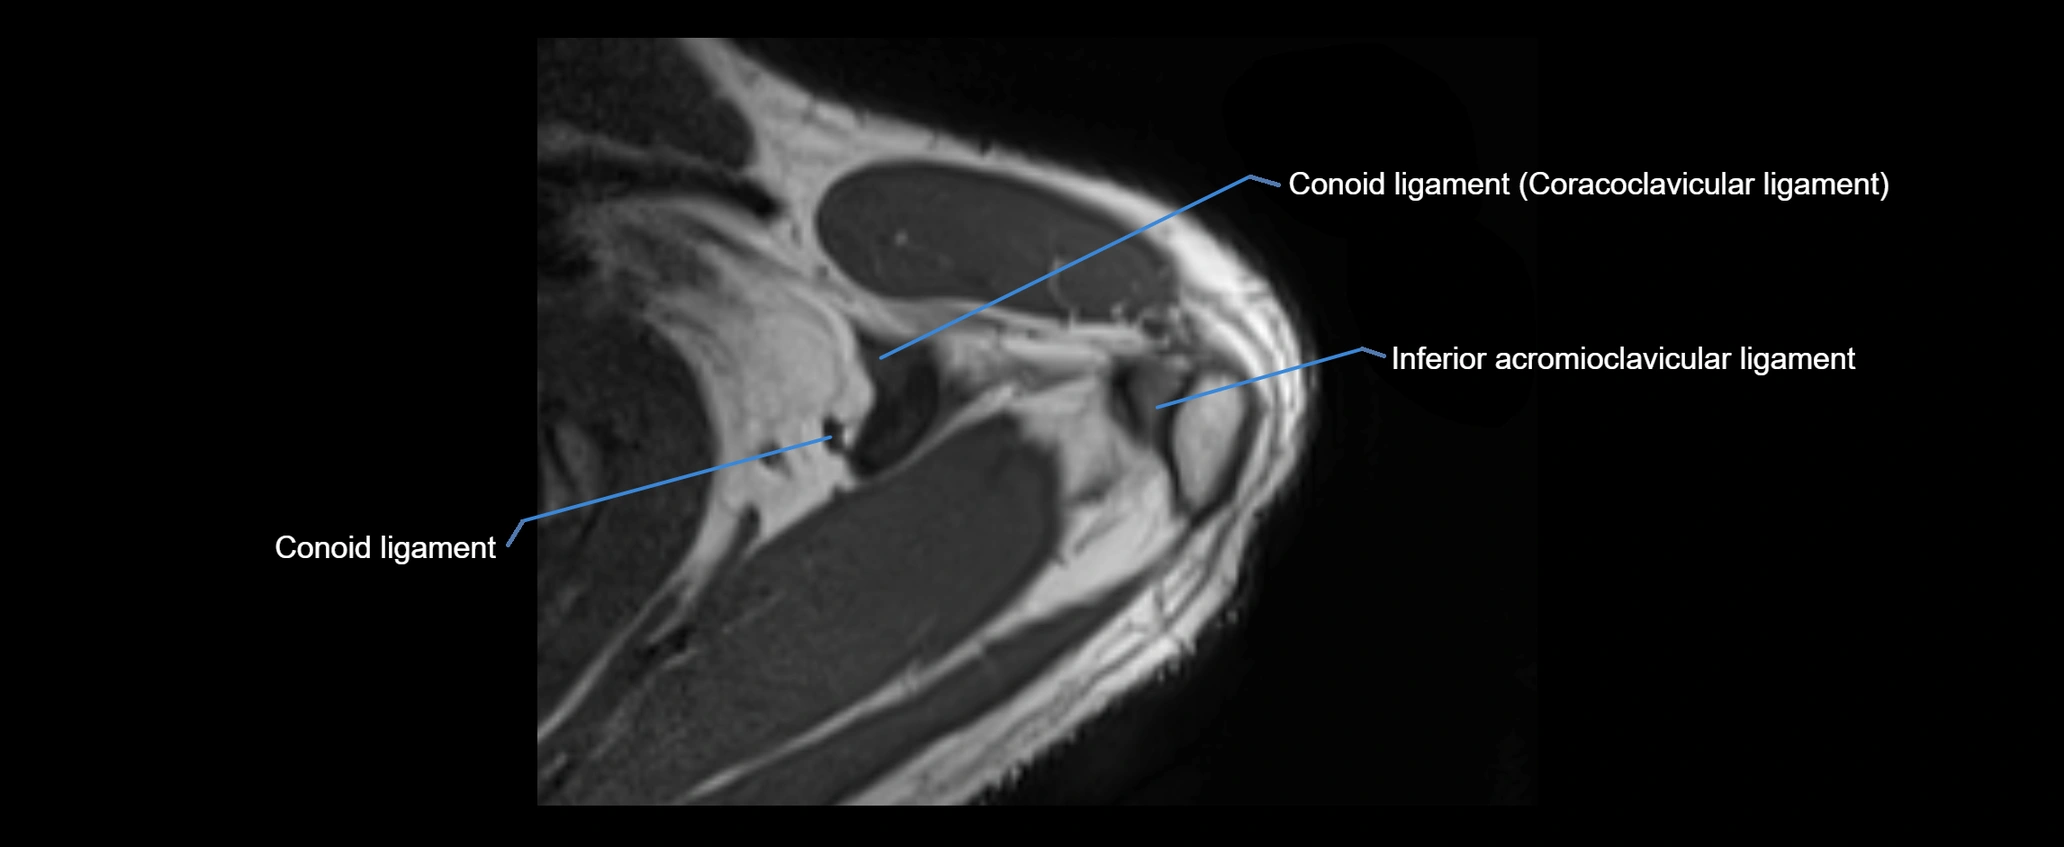

MRI images

image

MRI Appearance

• T1-weighted images:

• Normal ligament: Low signal (dark linear band) spanning acromion to clavicle.

• Surrounding fat planes: Bright, delineating the ligament clearly.

• Marrow of clavicle and acromion: Bright due to fatty content.

• Tears: Discontinuity or irregular thickening with intermediate-to-bright signal.

• Chronic injury: Thinning, fraying, or irregular low-signal fibers with adjacent scarring.

• T2-weighted images:

• Normal ligament: Low signal, homogeneous.

• Partial tear or sprain: Focal hyperintensity or thickening.

• Complete tear: Discontinuity with fluid-bright gap between clavicle and acromion.

• Associated edema: Bright signal in distal clavicle or acromion marrow.

• STIR:

• Normal ligament: Dark linear band.

• Injury or inflammation: Bright hyperintense signal in and around ligament fibers.

• Highlights periligamentous soft-tissue edema, especially in acute trauma.

• Proton Density Fat-Saturated (PD FS):

• Normal ligament: Low signal, uniform thickness.

• Partial tear or sprain: Bright signal or contour irregularity.

• Complete tear: Clear discontinuity with bright signal gap and joint effusion.

• Excellent for assessing joint capsule, coracoclavicular ligaments, and periarticular edema.